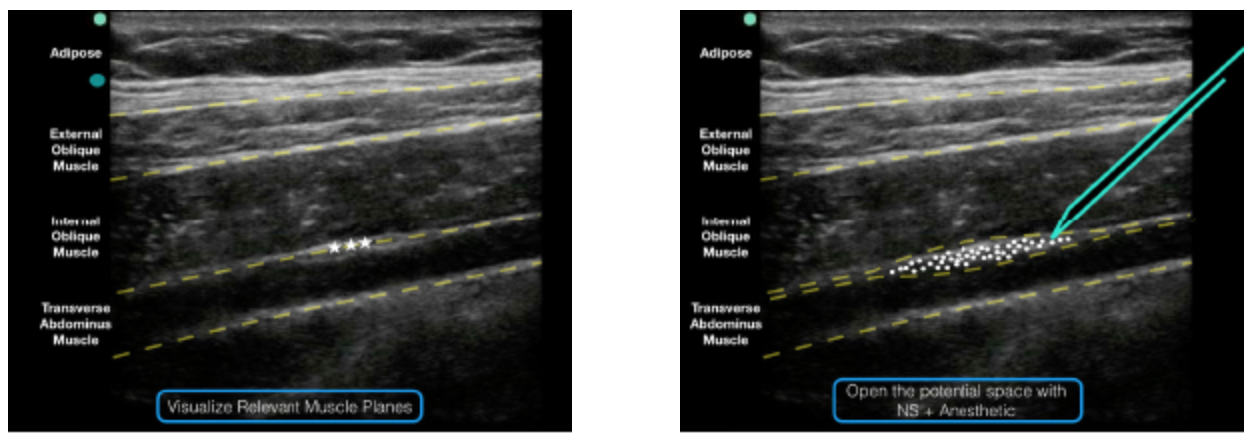

• Transverse orientation above the iliac crest at the mid- to anterior-axillary line (Figures 2) so that the external oblique, internal oblique, and transversus abdominis muscle layers are easily visualized (Figure 3)

• Place the needle in-plane (enter medial to lateral/posterior) and advance until the needle reaches the interfascial plane between the internal oblique and transverse abdominis muscles

• Inject anesthetic. Deposition can be confirmed by visualization of anechoic fluid tracking between the internal oblique and transverse abdominis muscles (Figure 3)

Figure 3: Note the external oblique, internal oblique, and transverse abdominis muscles on the ultrasound screen. The goal is to deposit anesthetic in the potential space just above the transverse abdominis muscle and just below the internal oblique…

Figure 3: Note the external oblique, internal oblique, and transverse abdominis muscles on the ultrasound screen. The goal is to deposit anesthetic in the potential space just above the transverse abdominis muscle and just below the internal oblique muscle.

Figure 4: An ultrasound representation demonstrating where anesthetic should be placed when performing a TAP block.